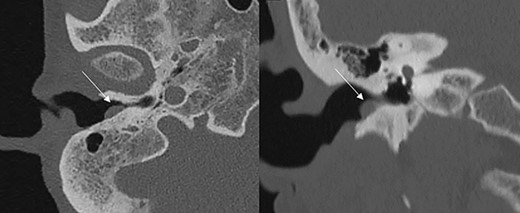

Axial and coronal CT scans showing a soft tissue mass (marked by the arrows) in the EAC without involvement of the tympanic membrane.